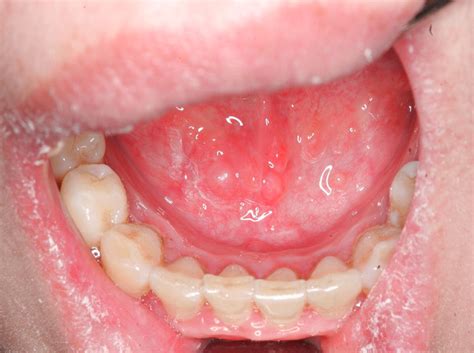

A mucocele is a fluid-filled swelling that typically appears on the inside of the lips, cheeks, or floor of the mouth. It occurs when a salivary gland is damaged, leading to the leakage of mucus into the surrounding tissue. This condition is generally harmless but can be uncomfortable and may affect speech and eating.

A mucocele on the roof of the mouth, also known as the palate, is less common than those found on the lips or cheeks. The roof of the mouth is a delicate area with several small salivary glands. When these glands are injured, a mucocele can form, causing a noticeable bump or swelling. This type of mucocele can be particularly bothersome due to its location, which can interfere with eating, drinking, and speaking.